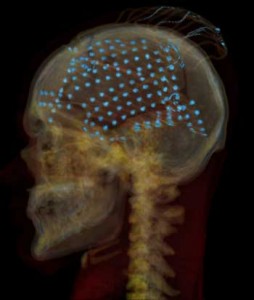

People undergoing brain surgery participated in the study, to determine the location of intractable seizures so that the area can be removed in a second surgery. Neurosurgeons typically cut a hole in the skull and safely place electrodes on the brain surface or cortex – in this case, up to 256 electrodes covering the temporal lobe – to record activity over a period of a week to pinpoint the seizures. For this study, 15 neurosurgical patients volunteered to participate.